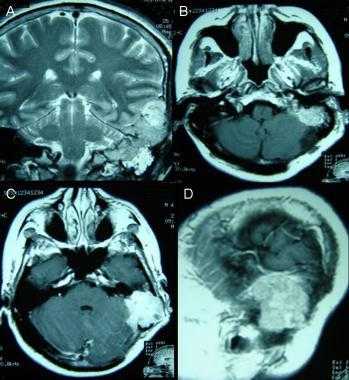

![image001]()

![image003]()

![image005]()

![image007]()

Метастазы головного мозга, фото. На КТ с контрастным усилением у пожилой пациентки (в верхнем ряду слева) с жалобами на головные боли выявлены множественные объемные образования в левом полушарии мозга, интенсивно накапливающие контрастное вещество. Образования имеют характерную форму в виде «кольца». На изображениях в нижнем ряду и вверху справа определяются множественные очаги в головном мозге: отчетливо видны округлые образования с более плотным «ободком» по периферии, располагающиеся в левой теменной доле.